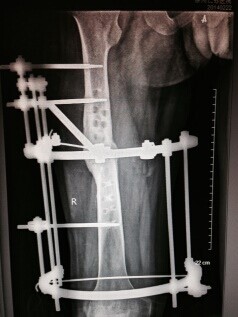

病例一:患者鹿XX,男,25岁,2011年1月3日发生车祸双下肢碾压伤,左下肢毁损,右胫骨开放性粉碎性骨折。外院急诊手术行左大腿截肢术,右小腿清创胫骨外固定支架固定术,术后右小腿感染,皮肤软组织坏死,长段胫骨外露,于2011年01月28日转来我院后行清创植皮修复等治疗。 于2011年05月07日行“右胫骨病灶清除+环形外固定支架固定+胫骨双段截骨滑移术”,术后开始行双段骨端滑移治疗(图一),根据X线片表现调整骨段滑移速度。2011年11月06日滑移骨段会师临床愈合。拆除外固定后2012年6月复查情况(图二)

图一 图二